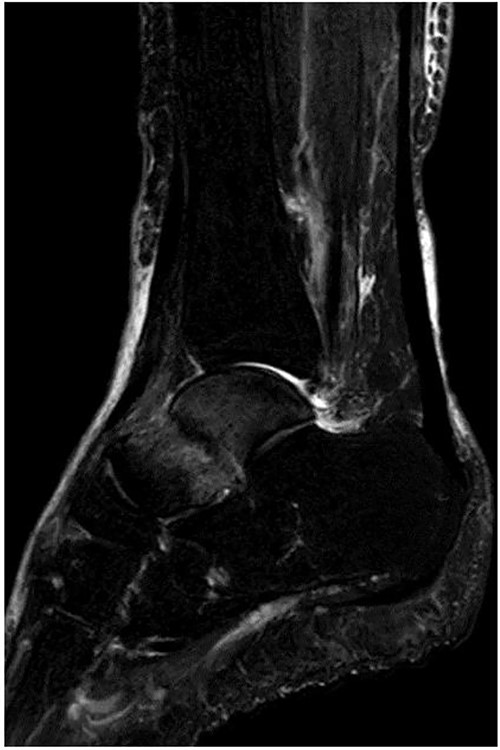

A 76-year-old female, who worked as a cleaner, complained of pain in her right ankle when going downstairs while working. She had medical history of only osteoporosis and had taking daily active vitamin D for >10 years. She was given conservative treatment for 1 month at a local clinic, however, her ankle pain persisted and so she visited our clinic. Physical examinations revealed tenderness and swelling at the anterior aspect of the ankle. Plain radiographs showed no obvious abnormal findings (Fig. 1). Magnetic resonance imaging (MRI) revealed a low signal linear line in the talar neck and a bone marrow edema around the line (Fig. 2). Non-contrast computed tomography (CT) demonstrated an obvious fracture line in the talar neck, however, the bone fragment was not displaced (Fig. 3). Based on medical histories, clinical and radiological findings, we diagnosed her with a fragility fracture of the talar neck associated with osteoporosis. Because the patient was elderly and it was difficult to treat using a prolonged non-weightbearing cast, we applied operative treatment to allow early rehabilitation. The operation was performed under spinal anesthesia in a prone position with an air tourniquet and a fluoroscopy. The posteromedial and posterolateral portals were created according to van Dijk et al. [10]. First, the posterior aspect of the talus was observed using a 4.0-mm diameter 30° arthroscope, and soft tissues around the talus (including synovium and adipose tissues) were removed with a 3.5-mm diameter motorized shaver. After confirming the posterior part of the talar body and the FHL, two 1.6-mm diameter guidewires were parallelly inserted from the posterior part of the talar body to the talar head by hindfoot endoscopy and fluoroscopy (Fig. 4A), and two cannulated 4.5-mm diameter double-threaded screws (Double Thread Screw, Meira, Nagoya, Japan) were inserted through the guidewires (Fig. 4B). The wound was sutured, and the operation was concluded (Fig. 5). Active range of motion exercises were allowed immediately after surgery, and a non-weightbearing short leg splint was worn for 1 week. Partial-weight bearing was permitted at 2 weeks and full-weight bearing was permitted at 4 weeks post-operatively. In addition, daily injections of teriparatide (Forteo, Eli Lilly and Company, Indianapolis, IN, USA) were introduced 2 weeks post-operatively. Eight weeks after the operation, the patient was able to return to work without pain or functional impairment. One year postsurgery, the patient was still working as a cleaner without any symptoms or complications.

Preoperative plain radiographs showed no obvious abnormal findings from the (A) anteroposterior and (B) lateral views.